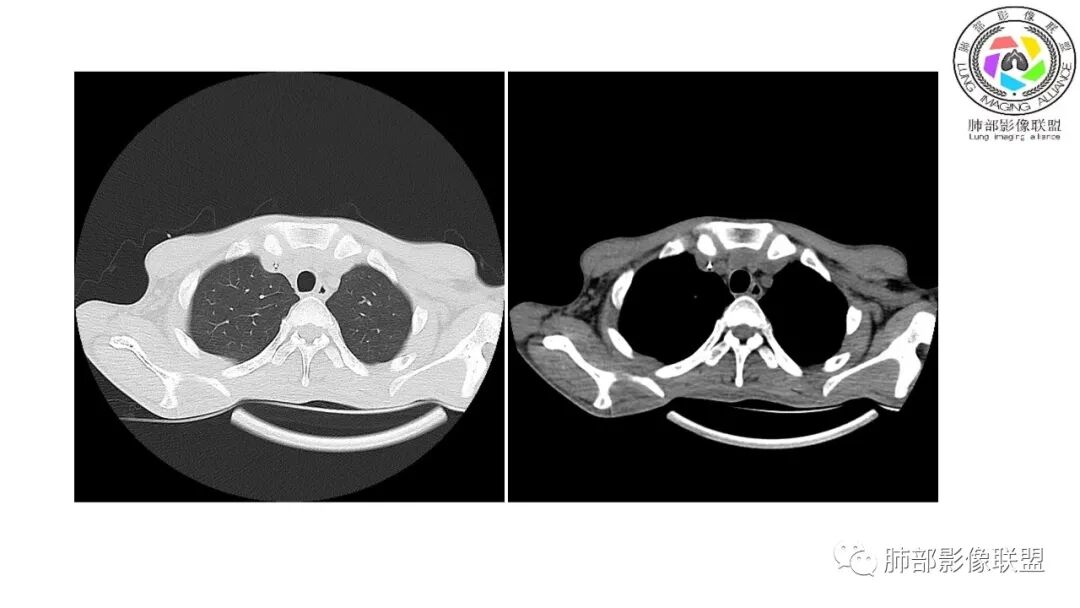

影像与临床:1.青年男性,HlV阳性,颜面部皮疹(未提供皮疹图像)、发热(高热),实验室CRP、PCT高,T-Spot阴性。2.右肺下叶空洞结节,壁厚不均,边界清楚,其内线状影,未见液平及钙化,未见卫星灶,纵隔淋巴结增大,双侧腋窝见增大淋巴结。心腔内低密度提示贫血可能。肝脾影增大,未见结节影及块影。腹膜后见多发增大淋巴结。

综合分析:本例肺部影像学改变并不具有特征性,空洞性病灶须与多种疾病鉴别,但年轻HIV阳性患者,高热,皮疹,肝脾增大,纵隔、腋窝、腹膜后见多发增大淋巴结等都强烈提示马尔尼菲篮状菌感染的可能性。